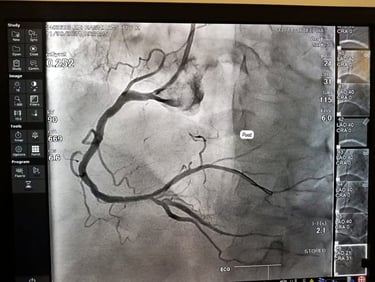

65 years old man from Azamgarh came to me with severe chest pain post CABG which was done in 2021.....

Patient was immediately taken for coronary Angiography which shows LIMA was 100% blocked which was stented Patient was completely pain free since then and living a good quality of life Today he came to meet me in my OPD in tamkuhi raj with smiling face....

Coronary Angiography / कोरोनरी एंजियोग्राफी

A test to detect blockages in heart arteries using dye and X-ray.